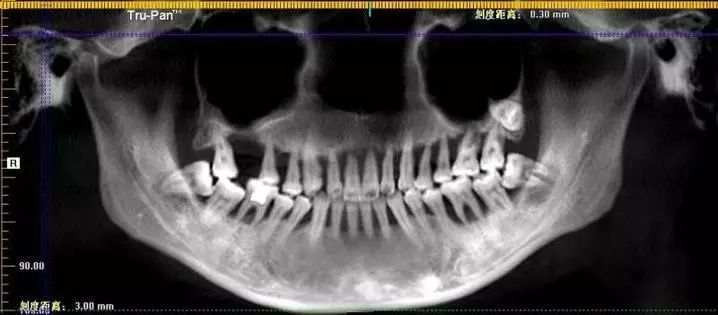

Ngờ đâu, sau khi thăm khám, các bác sĩ đưa ra yêu cầu Tiểu Minh phải nhổ cả hàm răng trên và trồng lại toàn bộ bằng răng giả. Nguyên nhân đến từ việc cô bị viêm nha chu quá lâu, nhưng không điều trị kịp thời khiến răng dần lỏng lẻo, mât đi chức năng nhai.

Ngược lại, để lâu, viêm nha chu có thể lan ra toàn miệng đồng thời gây viêm nhiễm. Nó cũng có thể xâm nhập từ nướu trên bề mặt ăn vào trong xương răng và phá hủy chân răng.